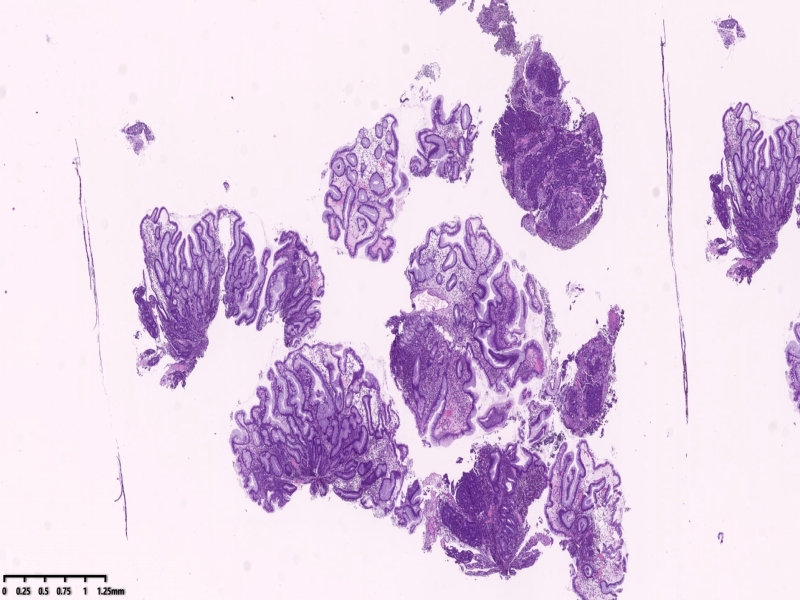

胃镜可见距离门齿35厘米一下可见一肿物凸向管腔,向下延伸至贲门口、胃体上部,管腔狭窄,胃镜勉强通过,肿物中央城溃疡状,覆盖白苔,周围坎坝杨改变,活检8块。

镜下所见:胃粘膜组织数块,炎症背景,其中3块固有层内可见细胞团,瘤细胞排列呈条索状迂回后呈巢状,巢的边缘瘤细胞呈栅栏状。细胞形态似柱状。